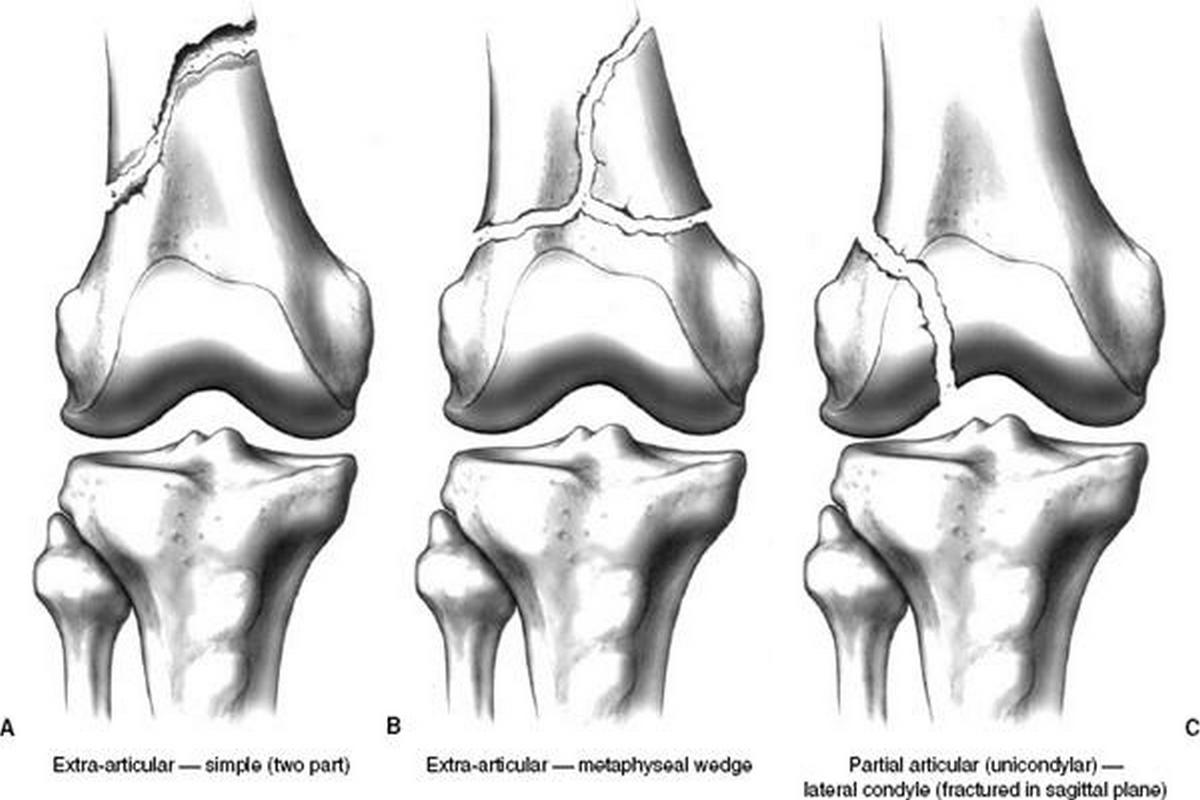

Κατάγματα κνημιαίων κονδύλων

Τα κατάγματα κνημιαίων κονδύλων αφορούν την άνω επιφάνεια της κνήμης, η οποία συμμετέχει άμεσα στη διαμόρφωση της άρθρωσης του γόνατος.

Εμφανίζονται συχνά μετά από τροχαία ατυχήματα, αθλητικούς τραυματισμούς ή πτώσεις. Τα συμπτώματα περιλαμβάνουν πόνο, οίδημα, δυσκολία στην κίνηση και συχνά αιμάρθρο.

Ιδιαίτερη σημασία έχουν οι συνοδές βλάβες σε μηνίσκους και συνδέσμους, οι οποίες επηρεάζουν την πρόγνωση. Εκτός από τις ακτινογραφίες, σχεδόν πάντα απαιτείται αξονική τομογραφία για λεπτομερή χαρτογράφηση του κατάγματος.

Μη παρεκτοπισμένα κατάγματα μπορούν να αντιμετωπιστούν συντηρητικά με ακινητοποίηση, αποφόρτιση και σταδιακή κινητοποίηση. Παρεκτοπισμένα ή ενδοαρθρικά κατάγματα απαιτούν χειρουργική ανάταξη και σταθεροποίηση με πλάκες ή βίδες. Η φυσικοθεραπεία είναι απαραίτητη για την πρόληψη δυσκαμψίας και δευτερογενούς αρθρίτιδας.